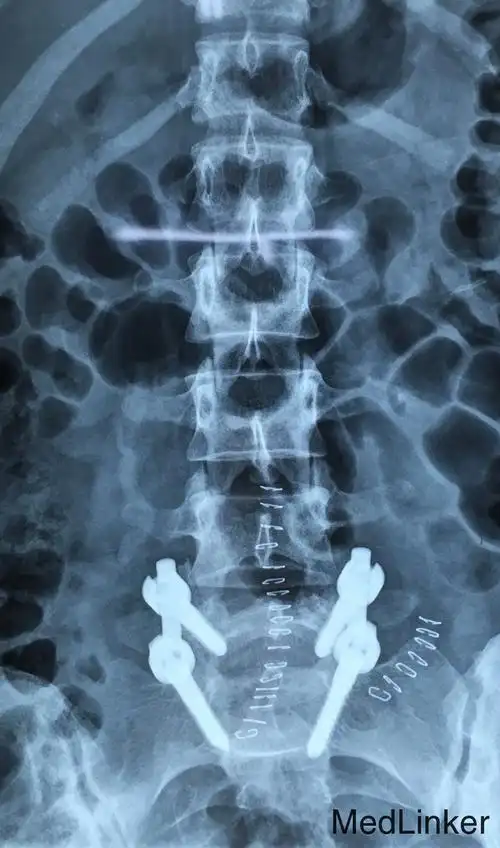

脊椎椎弓峡部裂,主要病因有先天性因素等,很少会出现无症状患者

腰椎峡部裂(lumbar spondylolysis)_信号_箭头_非手术治疗

腰椎峡部裂1例

【求助】是否为先天性椎弓根峡部裂?

年轻人腰痛警惕腰椎峡部裂